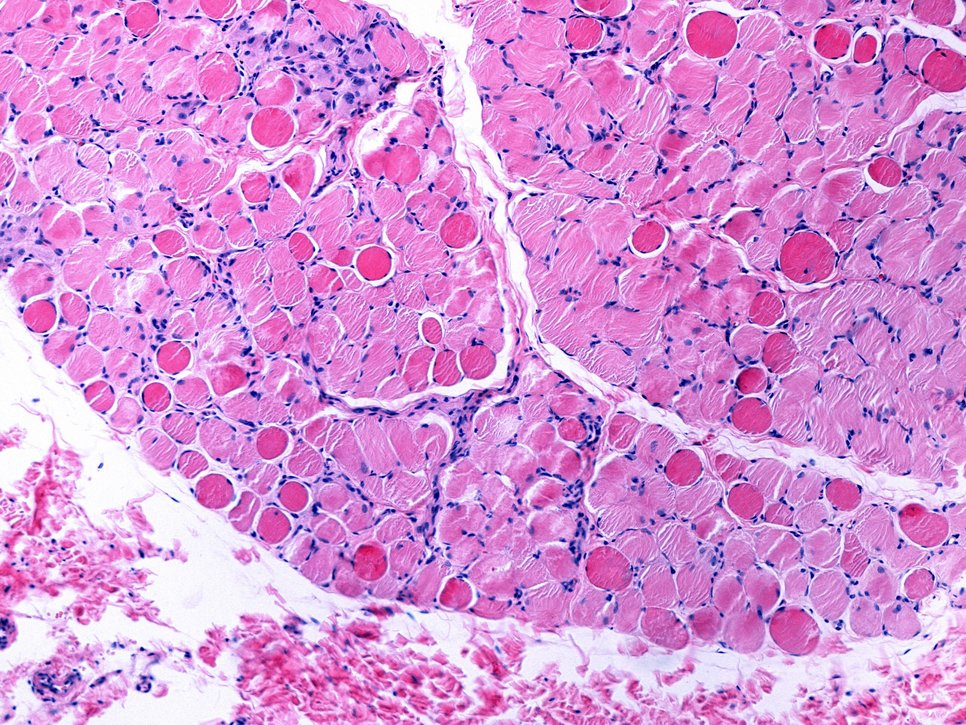

Duchenne muscular dystrophy (DMD) is a severe type of muscle disorder predominantly affecting boys. The disease is chronic and begins in childhood. The life expectancy of affected patients is significantly reduced. The disease, for which there is currently no cure, is caused by mutations in the dystrophin gene, which is located on the X chromosome. Dystrophin is important for cell membrane stability in muscle fibres. Due to the genetic defect, dystrophin is absent in these patients. As a consequence, muscle cells are restricted in their function and the musculature is increasingly weakened.

The Max Planck scientists have now shown in cultured cells from DMD patients that the dystrophin mRNA fragments increase utrophin production in the affected cells. ‘The mechanism behind this observation is transcriptional adaptation. By regulating the dystrophin mRNA decay mechanism, it is possible to control utrophin production in these cells. This provides a starting point for a therapy,’ says Falcucci.